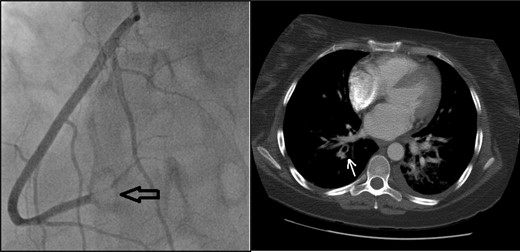

She received thromboembolic prophylaxis on admission. Shortly after, she developed syncopal episodes. ECG findings and rising cardiac enzymes confirmed a myocardial infarct. Computed tomography (CT) scan showed evidence of a pulmonary embolus. In light of the above, the patient was transferred to the intensive care unit and received therapeutic anticoagulation. Subsequently, a coronary angiography revealed a thromboembolic closure of the distal right coronary artery (Fig. 1) which was treated with partial thrombectomy. The patient remained stable but her echo-cardiogram showed severely raised pulmonary artery pressure (59 mmHg).

Coronary angiogram (left): note the visible blockage in the distal right coronary artery (black arrow). CT thorax (right): pulmonary embolus in the subsegments of the right upper lobe (white arrow).